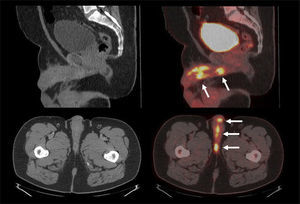

Aunque el PET/CT no figura en el algoritmo habitual de estudio de etapificación, ha ganado terreno rápidamente gracias a ciertos radiotrazadores específicos desarrollados en los últimos años, principalmente aquellos basados en el trazador PSMA (Prostate Specific Membrane Antigen) (22). Varias publicaciones destacan la alta correlación del PET/CT Ga68-PSMA con la RM de próstata al evaluar el tumor primario (23), y su superioridad diagnóstica en etapificación N, al detectar pequeñas adenopatías regionales que pasan inadvertidas con TC o RM (Figura 7) (24). Al estudiar preoperatoriamente a pacientes de riesgo intermedio y alto, Van Leeuwen et al encontraron una sensibilidad de 64% y especificidad de 95% en detección de linfonodos, todos ellos <10 mm, es decir negativos a la TC (25). Ellos sugieren que el PET/CT Ga68-PSMA debiera reemplazar en el futuro a los métodos tradicionales de etapificación N. Los falsos negativos obtenidos corresponden mayormente a ganglios metastásicos <5 mm, los que siguen siendo un desafío diagnóstico para las técnicas de imagen actuales.